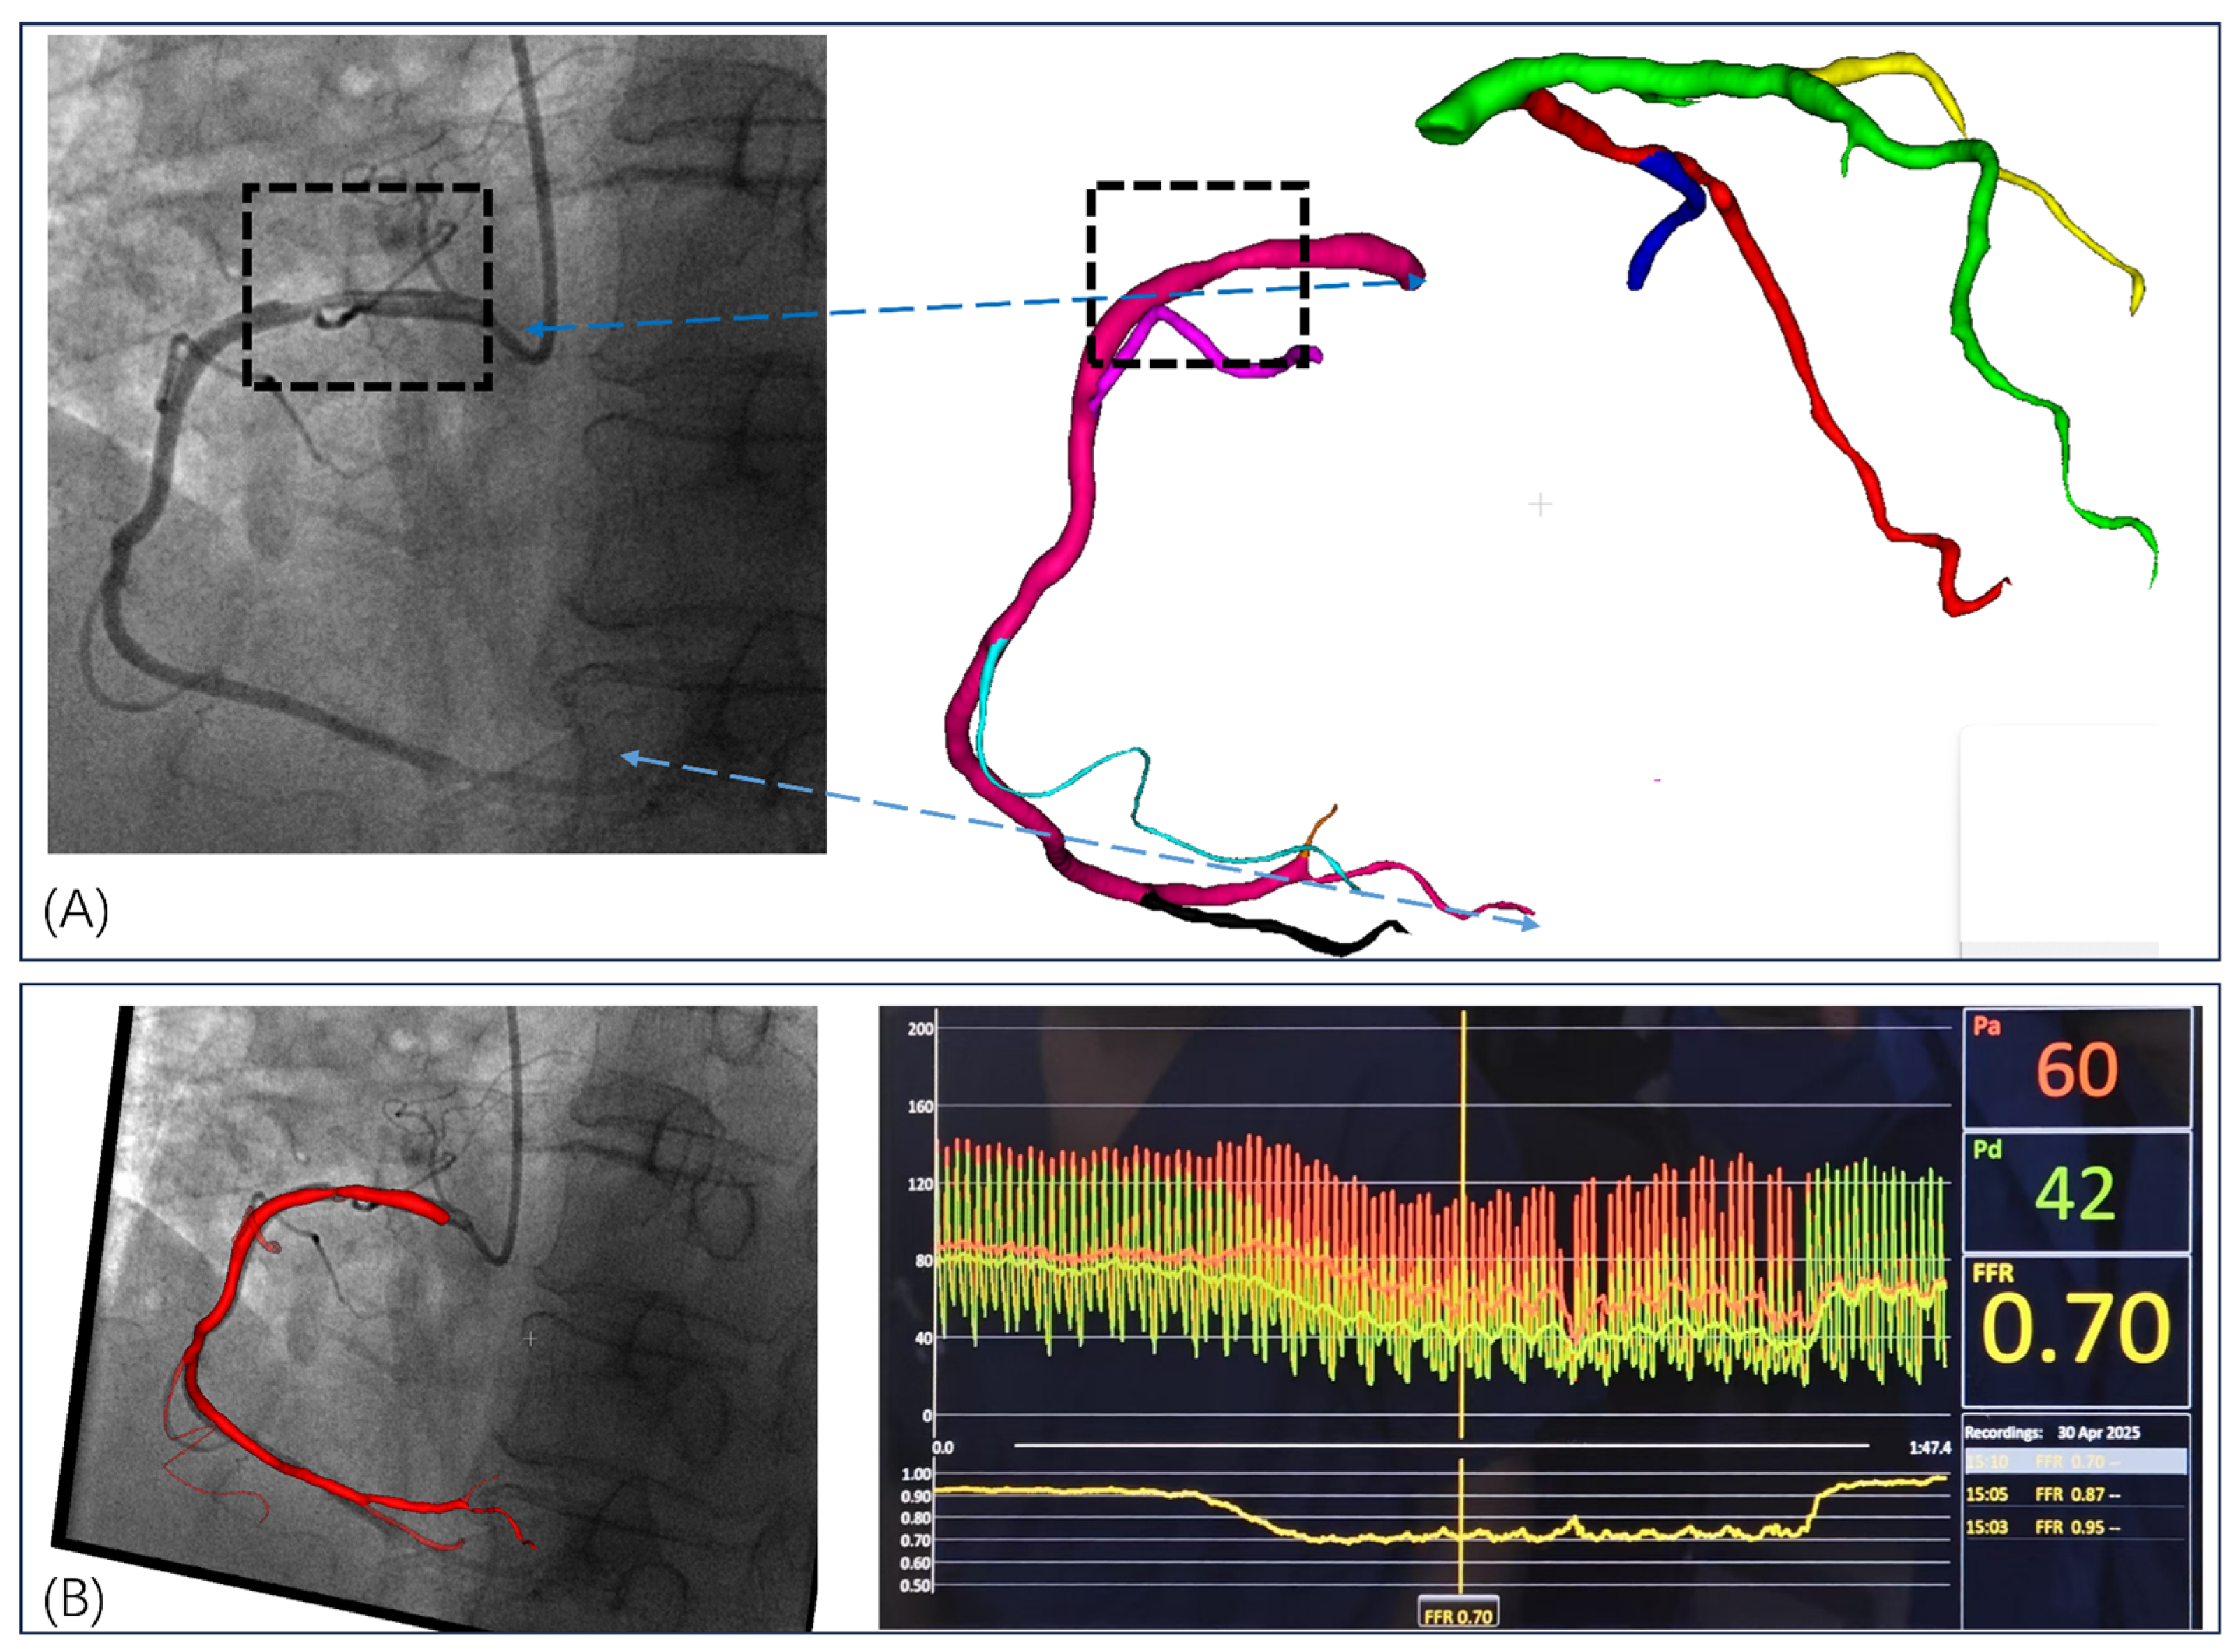

3.1. Invasive FFR Assessment

| Case | Vessel | Invasive FFR | Static FFRCT | Dynamic FFRCT |

|---|---|---|---|---|

| 1 | RCA | 0.70 | 0.742 | 0.720 |

| 2 | LAD | 0.78 | 0.825 | 0.797 |

| 3a | LAD | 0.78 | 0.818 | 0.811 |

| 3b | LCX | 0.94 | 0.961 | 0.952 |